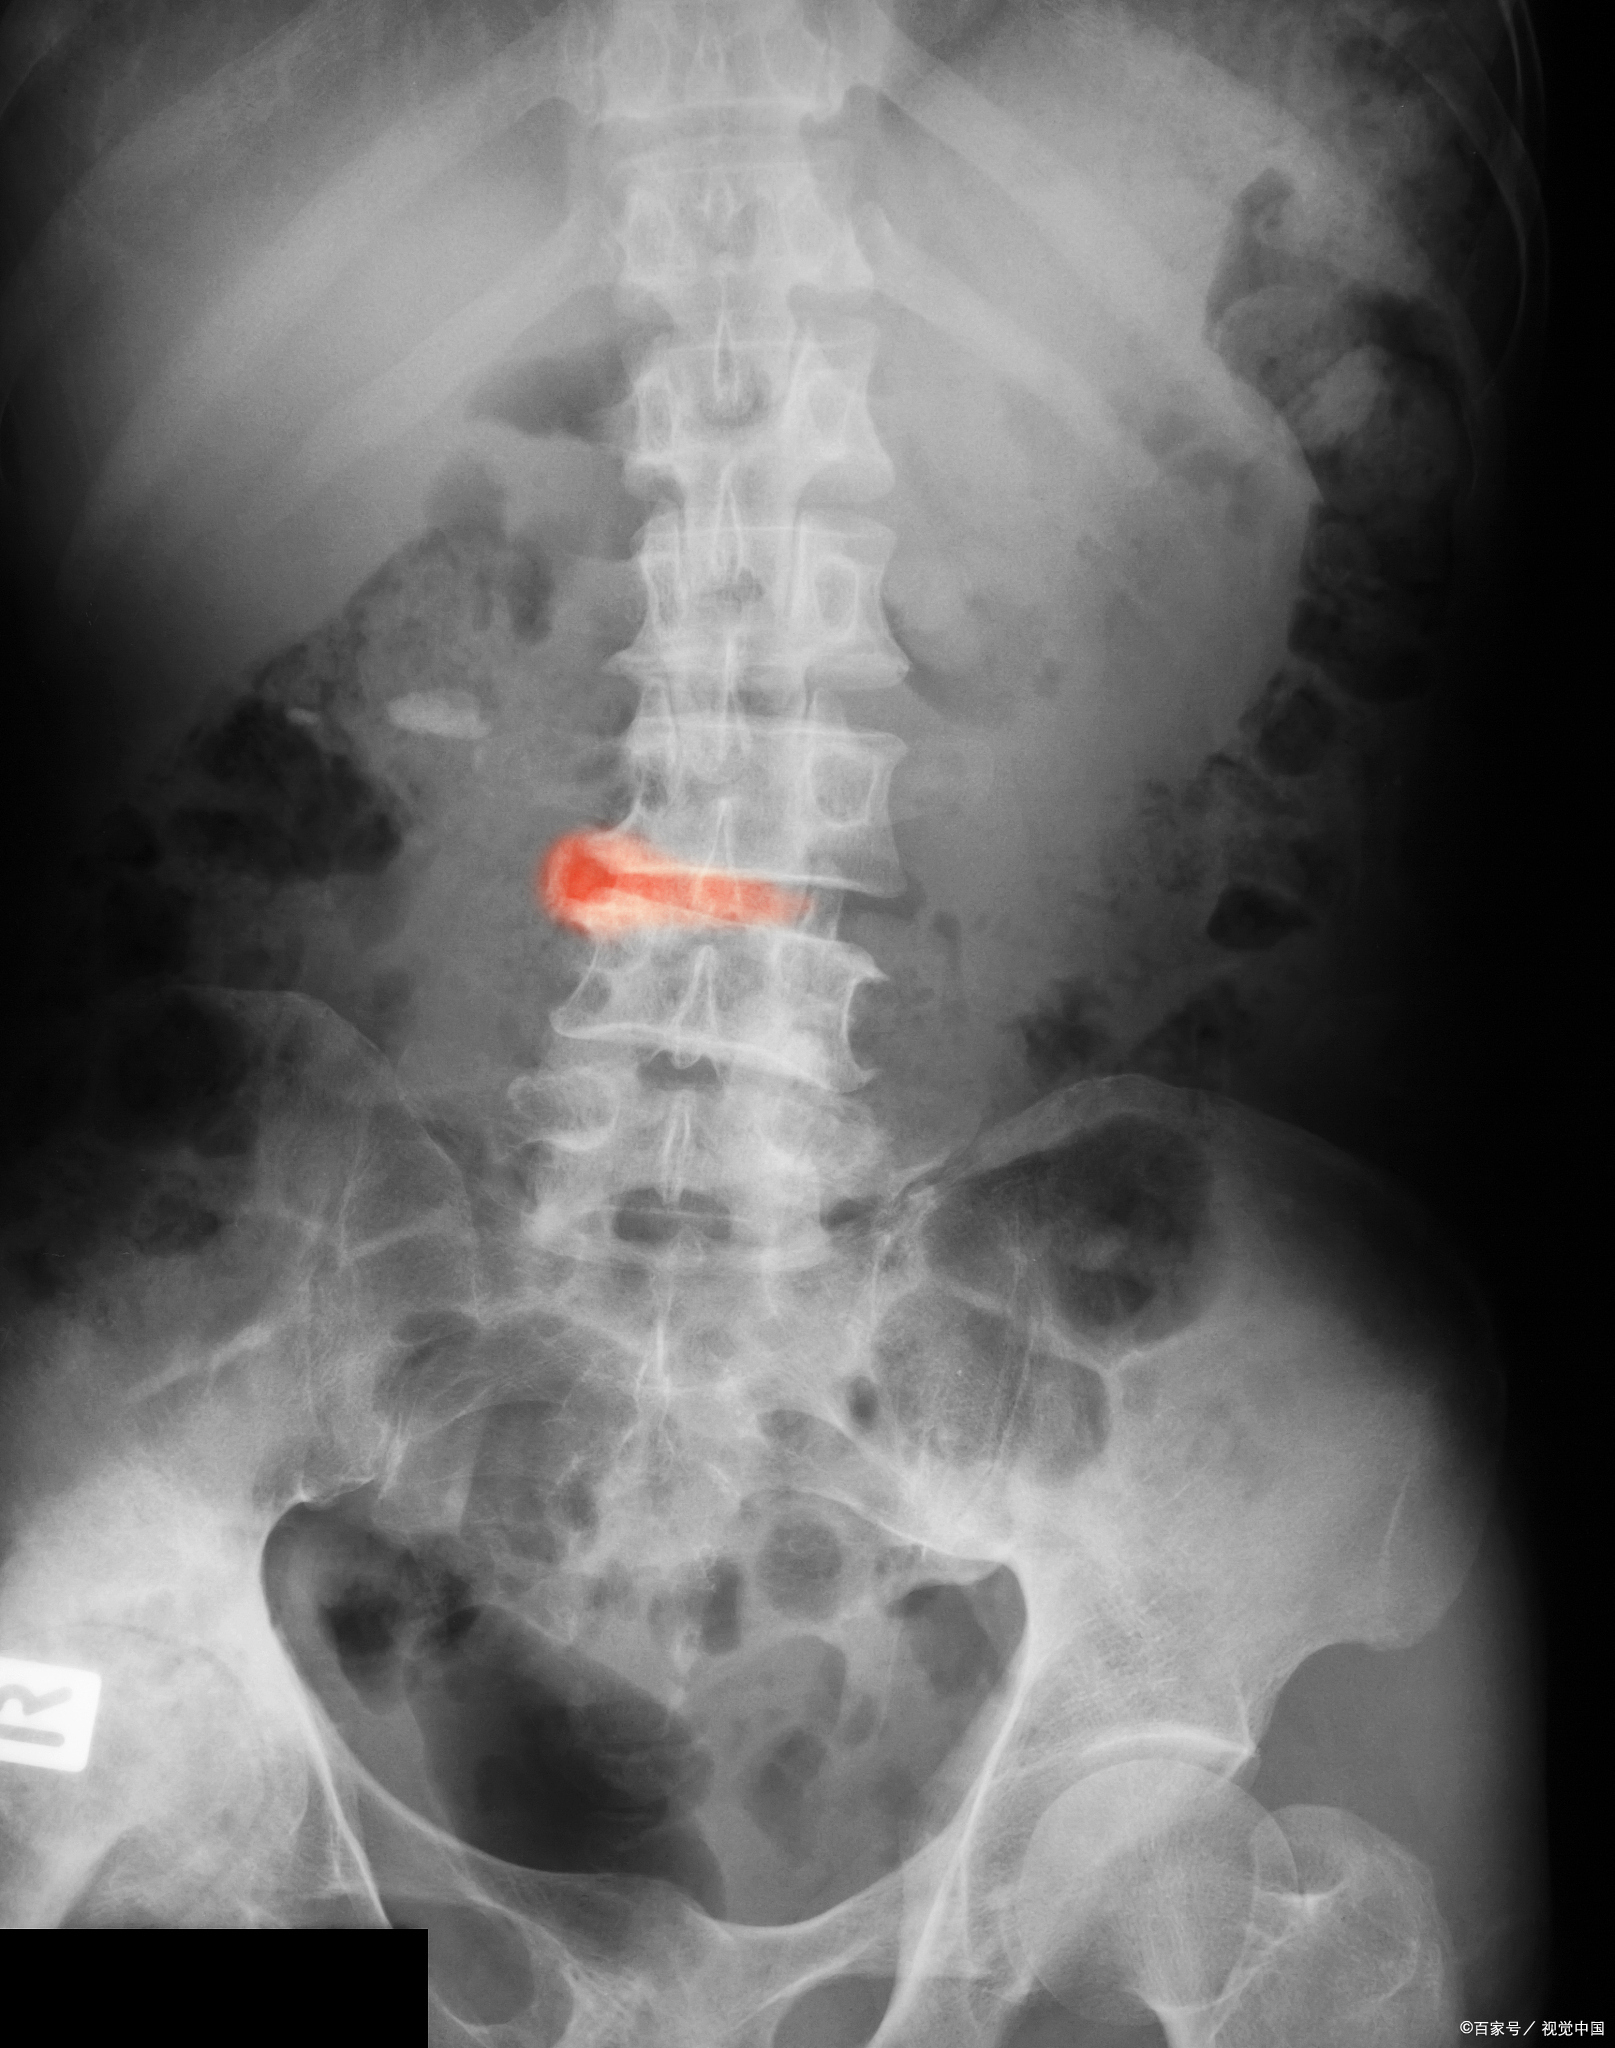

强直性脊柱炎,压缩性骨折,移行椎